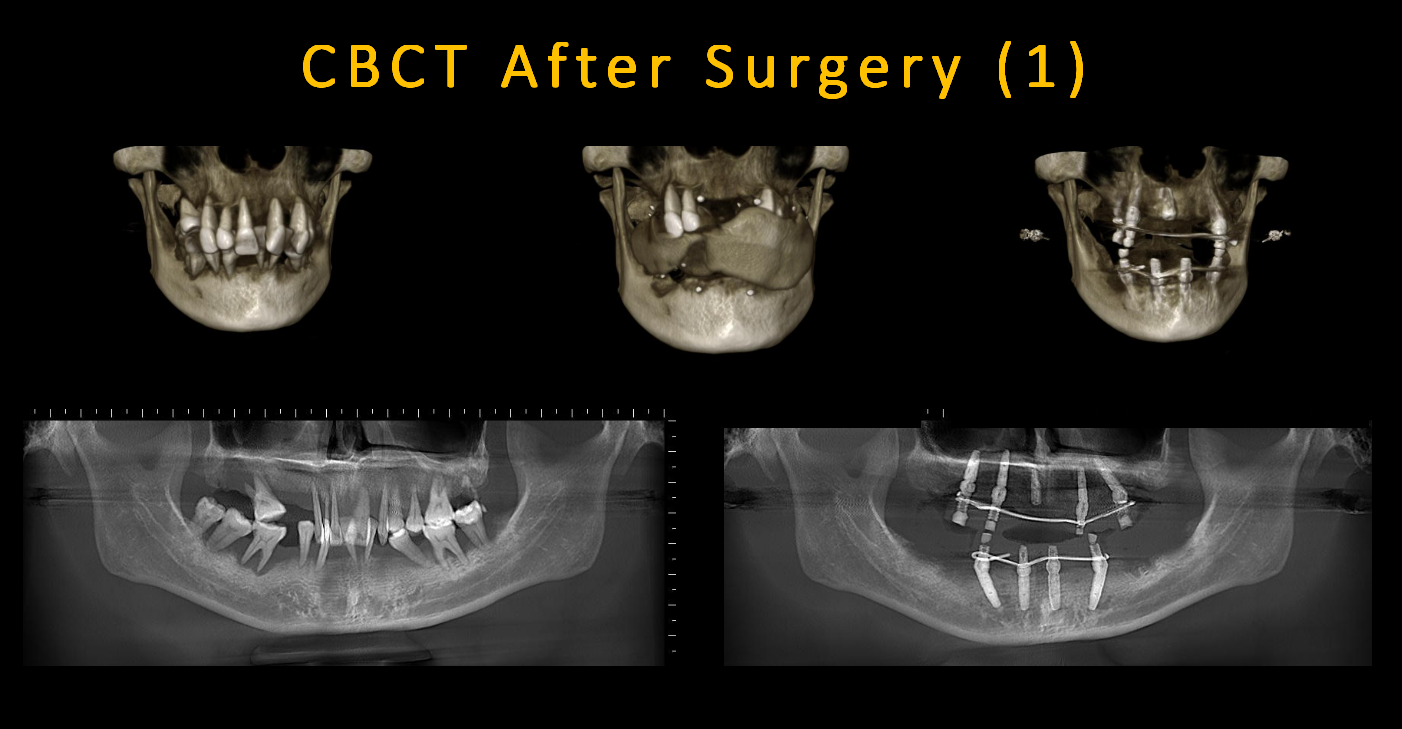

CT showed that the alveolar bone of the whole mouth was horizontally absorbed to 1/3 of the root tip

Implants(A zone=Right upper jaw、B zone=Left upper jaw、C zone=Left lower jaw、D zone=Right lower jaw)

A4 build 3.5*12mm, upper Angle base station (17 degrees)

A6 is implanted with 4.0*10mm upper straight base platform

A1 is implanted 3.5*10mm, and the upper Angle base platform (30 degrees) is required at the later stage.

B3 implant 3.5*12mm, upper Angle base (17 degrees)

B6 implant 3.5*12mm, upper Angle base platform (30 degrees)

C2 was implanted with 3.5*12mm upper straight base platform

C5 implant 3.5*12mm, upper Angle base platform (30 degrees)

D2 was implanted with 3.5*12mm upper straight base platformD5 implant 3.5*12mm, upper Angle base platform (30 degrees)